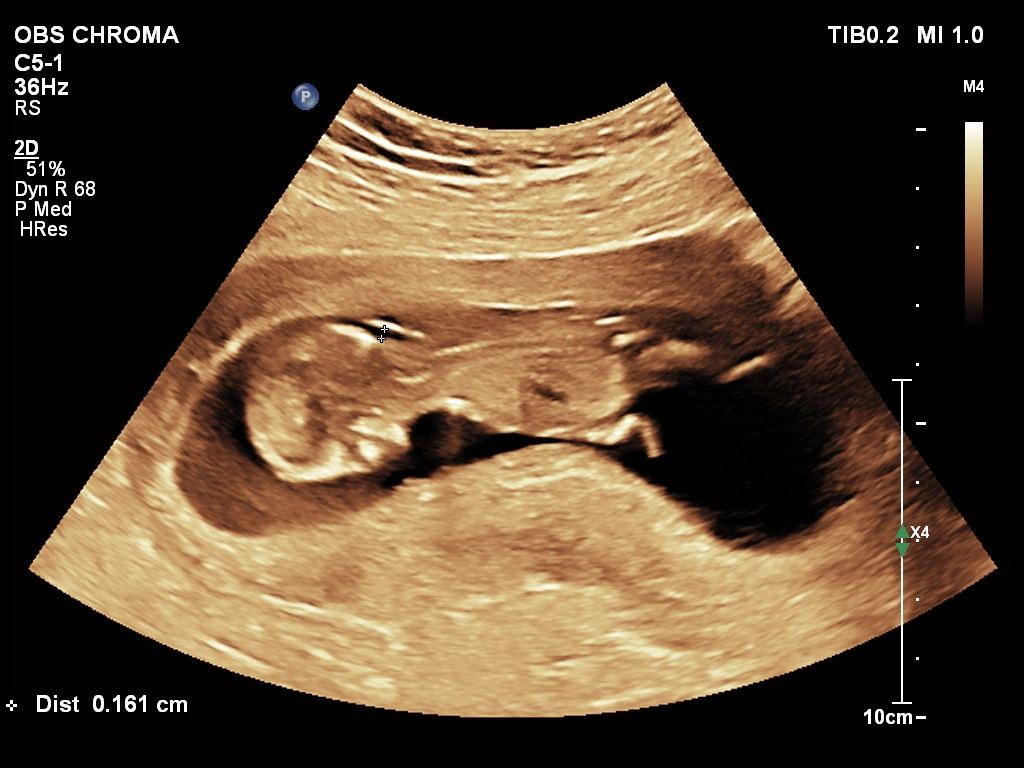

🔹 Anomaly Scan (Level II Ultrasound)

Anomaly Scan is a detailed ultrasound performed during pregnancy (usually between 18 and 22 weeks) to check the baby’s development. It helps detect structural abnormalities in the brain, heart, spine, kidneys, and other organs. This scan ensures your baby is growing normally and helps doctors identify any potential complications early. If you are looking for a reliable anomaly scan in Kathmandu, an early and accurate diagnosis is essential for a safe pregnancy.